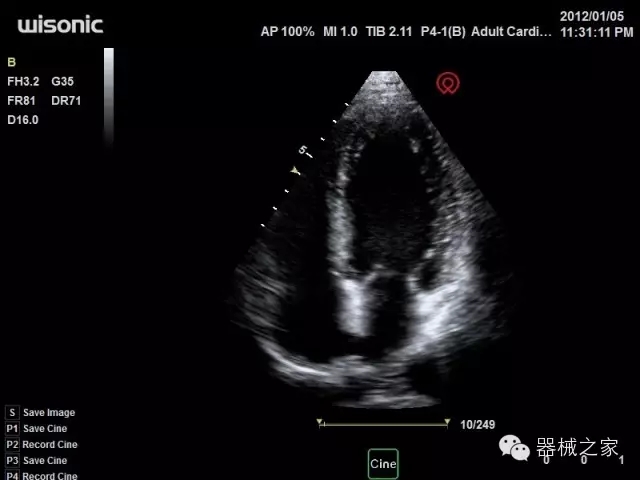

臨床圖片賞析

產(chǎn)品特點(diǎn)

·全球目前唯一一款配備主機(jī)雙探頭接口,整機(jī)重量(含電池)在5公斤以內(nèi)的便攜式彩超;